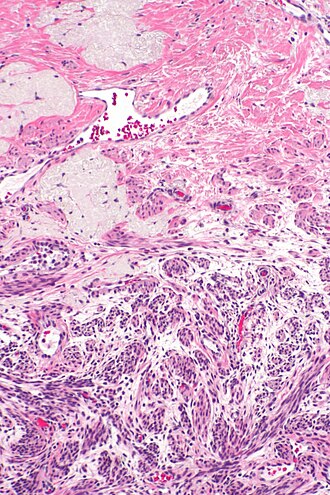

Ablated_endometrium. H&E stain. | |

| LM | endometrium completely or partially replaced by hyaline material and fibrosis |

Microscopic

Features:

- Endometrium completely or partially replaced by:

- Hyaline material, fibrosis.

UTERUS, UTERINE CERVIX, TOTAL HYSTERECTOMY: - SUPERFICIAL FIBROSIS AND HYALINE CHANGE OF THE UTERINE LINING -- COMPATIBLE WITH PRIOR ABLATION. - UTERUS WITH LEIOMYOMAS. - UTERINE CERVIX WITHIN NORMAL LIMITS.